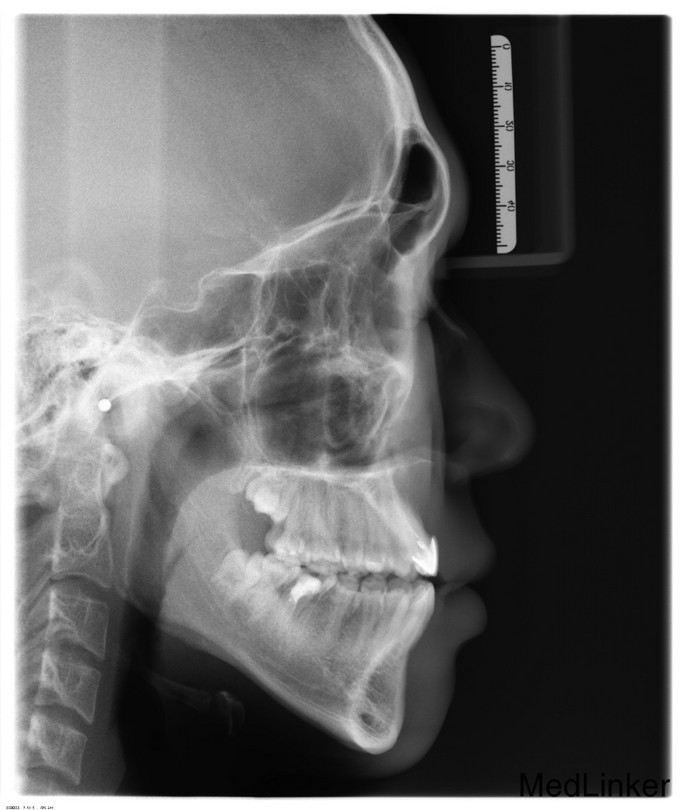

正颌术后半年要求取出钛板

双侧面部基本对称,张口度3.5cm,张口型“↓”,双侧髁突动度正常,张闭口未闻及关节弹响。口内检查:双侧下颌前庭沟可见手术瘢痕。左下6颊侧可见一瘘管,轻压痛,无溢脓。36牙合面大面积充填物,46残冠。双侧头颈淋巴结未触及明显异常。

诊断:1.双侧下颌正颌术后钛板存留2.36、46残冠,全麻下行双侧下颌骨钛板取出术+双侧下颌骨邻近瓣转移修复术+36、46拔除术,手术经过顺利,麻醉满意,术后予消炎、消肿等对症治疗。